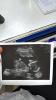

Мои переживания меня до гроба доведут 💆🏻♀️

Я в валдберис покупала , до первых шевелений слушала каждый день сердечко